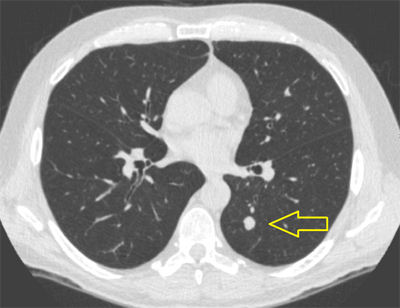

People are getting CT scans more often, and when these CT scans involve the lung it is common to find small spots, which are called lung nodules. Most lung nodules found are not cancerous, and are usually due to some current or past infection. However, a nodule is more or less likely to be cancerous based on the size, appearance, and growth rate. The likelihood also depends on the person’s age and smoking history. If these factors suggest a particular lung nodule is likely to be cancerous, then a biopsy is usually done. On the other hand, if a particular lung nodule is not very likely to be cancerous, we often monitor for growth by repeating CT scans over time. Sorting out which lung nodules are serious and which are not usually requires specialty care by a pulmonologist.